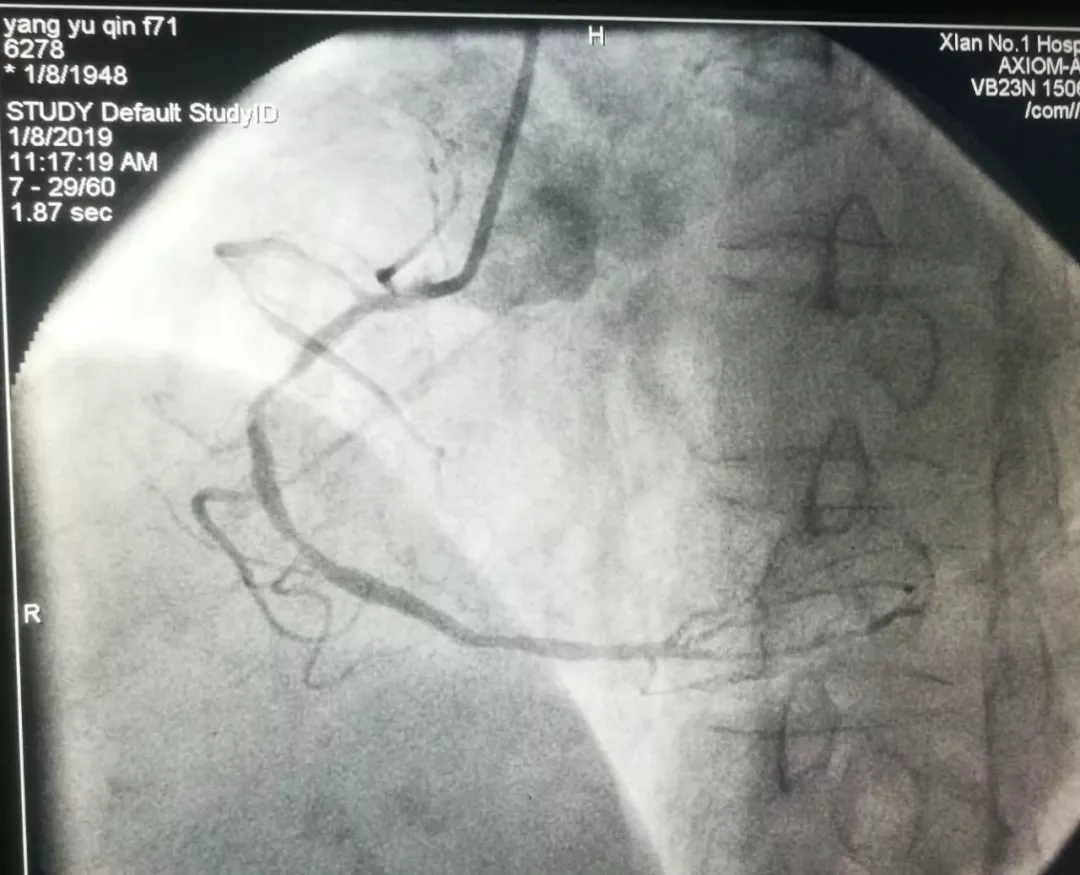

记文理病区开展首例冠状动脉造影术、冠状动脉支架植入术